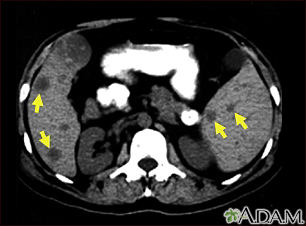

Abdominal CT scan

An abdominal CT scan is an imaging test that uses x-rays to create cross-sectional pictures of the belly area. CT stands for computed tomography.

A computer creates separate images of the belly area. These are called slices. These images can be stored, viewed on a monitor, printed on film or saved to a disk. Three-dimensional models of the belly area can be made by stacking the slices together.

An abdominal CT scan makes detailed pictures of the structures inside your belly very quickly.